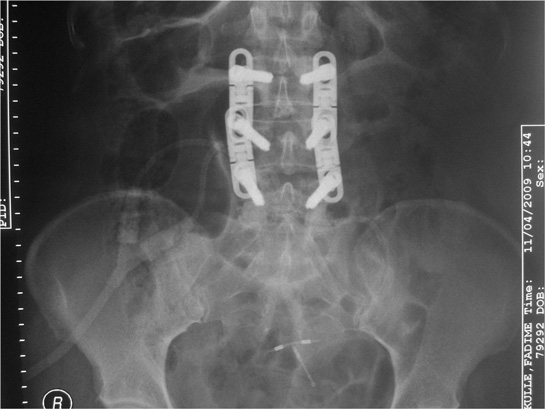

Bele Platin Takılması

Bele platin takılması, bel bölgesindeki yaralanmalar ve dejeneratif hastalıkların tedavisinde kullanılan bir cerrahi yöntemdir. Bu işlem, omurganın stabilitesini artırarak ağrıyı azaltmayı amaçlar. İlgili süreçler, iyileşme süreci ve olası komplikasyonlar hakkında bilgi sunulmaktadır.

Bele platin takılması, bel bölgesinde meydana gelen yaralanmaların, kırıkların veya dejeneratif hastalıkların tedavisinde kullanılan cerrahi bir yöntemdir. Bu işlem, omurganın stabilitesini artırmak ve ağrıyı azaltmak amacıyla gerçekleştirilir. Bu makalede, bele platin takılmasının nedenleri, prosedürü, iyileşme süreci ve olası komplikasyonları ele alınacaktır. 1. Bele Platin Takılmasının NedenleriBele platin takılması, çeşitli tıbbi durumlar nedeniyle gerekli hale gelebilir. Bu nedenler arasında şunlar bulunmaktadır: